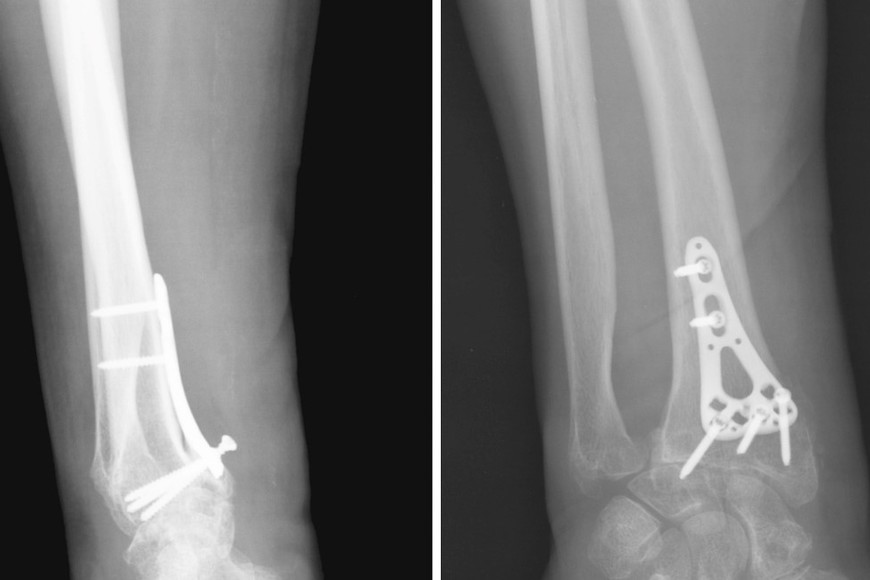

La Disposición 8703/2025 prohibió el uso, comercialización y distribución de todos los productos elaborados por Juratec Medical S.R.L., empresa con sede en Rosario, luego de comprobar que fabricaba placas, tornillos y otros insumos de osteosíntesis sin el registro correspondiente.

Las inspecciones revelaron que la firma entregaba material quirúrgico sin identificación, sin esterilización adecuada, sin órdenes formales de producción y sin documentación de respaldo.

Incluso se verificó la venta de productos a obras sociales, ortopedias y prestadores de varias provincias, pese a que la empresa no contaba con registros vigentes.

El organismo también señaló que uno de los productos históricos de la marca —el sistema ortopédico PM 2364-1— se encontraba vencido desde noviembre de 2023, lo que lo vuelve ilegal para su comercialización. Ante un patrón reiterado de incumplimientos, la ANMAT inició un sumario sanitario.